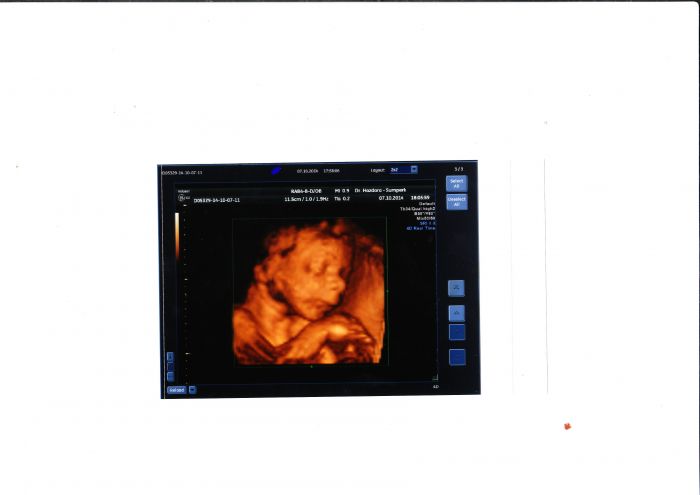

Brozanko máš krásné fotečky

a na té druhé jak si spokojeně spinká.